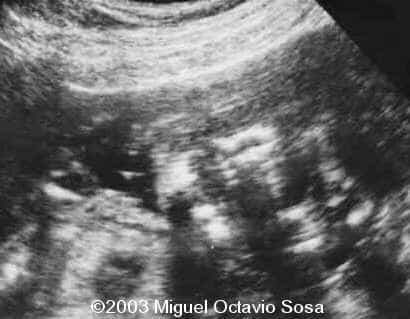

19-year-old primigravida. During third week of pregnancy, she is vaccinated with anti-measles vaccine, without knowing about the pregnancy. There are no important details before the pregnancy. These are images of the face of the fetus. Pay specific attention to the midface.

19-year-old primigravida. During third week of pregnancy, she is vaccinated with anti-measles vaccine, without knowing about the pregnancy. There are no important details before the pregnancy. At 22nd week, an ultrasound is performed demonstrating a single nasal channel on the left side and absence of right nostril.